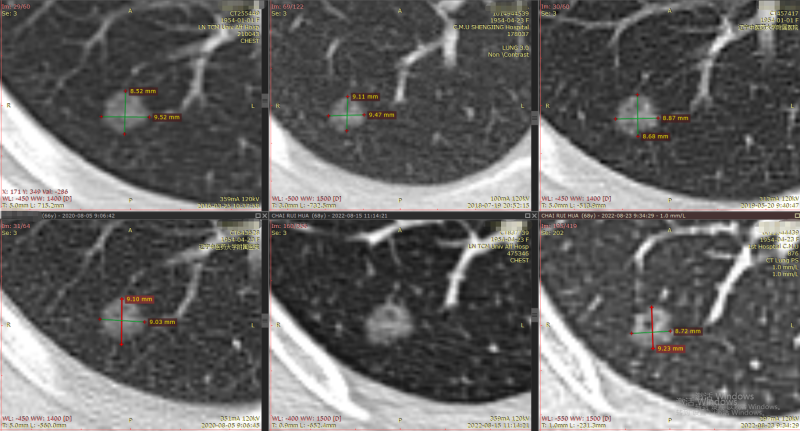

结节1:

2013年

2016年-2022年

右肺下叶背段纯磨玻璃结节,最大截面约0.9cm×0.9cm,平均CT值约-431Hu,结节呈类圆形,其中可见小空泡,病灶边界清楚,与9年前CT片比较,病灶密度、大小均无明显变化,考虑为微浸润性腺癌-浸润性腺癌,以微浸润性腺癌可能性大。